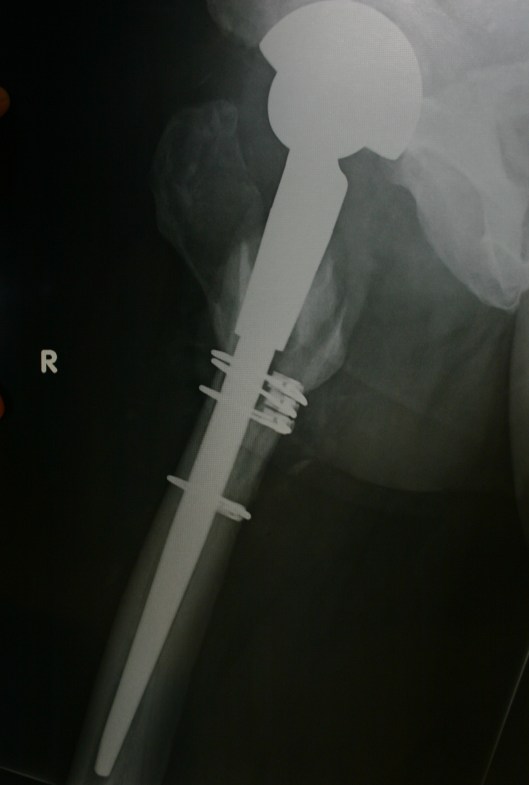

Visited the surgeon and he was very happy with the progress – Day 26 post Operation. Total hip Revision – from S&N Birmingham Spectron Metal on Metal to Zimmer Revision Ceramic on Ceramic Hip.

Considering that I had the femur split, two bone grafts and new hip implants (both press fit), the healing of the bone, tissue and wound is great and in terms of mobility of the new joint all is great!

Below are two of the X-Rays taken on the 26th Sept 2011. The marks on the X-Rays are courtesy of the younger person in the house who spilled their drink…